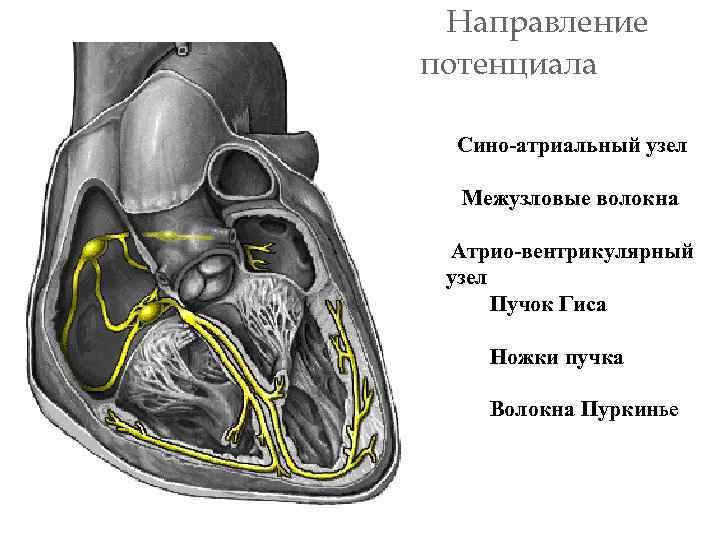

Авторитмические клетки во внутренней проводящей системе сердца генерируют потенциалы действия, которые распространяются по сердцу, вызывая сокращения сократительных клеток.

Авторитмические клетки во внутренней проводящей системе сердца генерируют потенциалы действия, которые распространяются по сердцу, вызывая сокращения сократительных клеток.

действия Направление потенциала Сино-атриальный узел Межузловые волокна Атрио-вентрикулярный узел Пучок Гиса Ножки пучка Волокна Пуркинье

действия Направление потенциала Сино-атриальный узел Межузловые волокна Атрио-вентрикулярный узел Пучок Гиса Ножки пучка Волокна Пуркинье